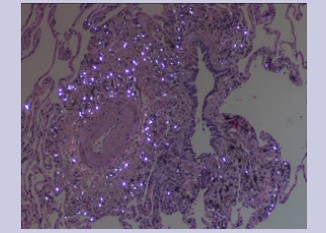

Physical exam was benign. Complete blood count and immunological panel were within normal limits. Spirometry, lung volumes and diffusion capacity were within normal limits. Chest x-ray (Figure 1) showed faint reticular opacities prominent in the mid to lower lobes. Computed Tomography (Figure 2) of the chest showed a diffuse mosaic attenuation pattern. There were multiple pulmonary nodules noted in the right middle lobe. There was no lymphadenopathy. Transthoracic echocardiogram showed impaired left ventricular relaxation with normal LV ejection fraction. Bronchoscopy and transbronchial biopsies of the right upper, middle and lower lobes were performed. Histopathology (Figure 3, Figure 4) revealed mild, nonspecific chronic inflammation. Acid-fast bacilli and fungal stains were negative. There was no evidence of malignancy. Given the persistent symptoms and abnormal CT findings, wedge biopsy of the right upper, middle and lower lobes was performed. Wedge resections showed alveolated lung with expansion of peribronchiolar interstitium by black dust-laden macrophages and dust macules. There were areas of peribronchiolar fibrosis with birefringent silicate and silica material within the interstitium and macrophages. Based on her history of exposure to stone grinding, charcoal and wood burning stoves along with the histopathologic findings consistent with mixed dust pneumoconiosis, she was diagnosed with "Hut Lung” or Domestically Acquired Particulate Lung Disease.

Figure 3: Histopathology showing birefringent silicate material within the interstitium.